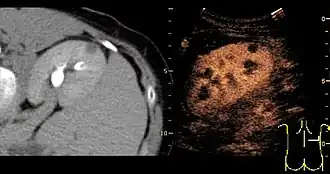

Kidney

A CT scan is the first choice modality for workup of solid masses in the kidneys. Nevertheless, hemorrhagic cysts can resemble renal cell carcinomas on CT, but they are easily distinguished with Doppler ultrasonography (Doppler US). In renal cell carcinomas, Doppler US often shows vessels with high velocities caused by neovascularization and arteriovenous shunting. Some renal cell carcinomas are hypovascular and not distinguishable with Doppler US. Therefore, renal tumors without a Doppler signal, which are not obvious simple cysts on US and CT, should be further investigated with contrast-enhanced ultrasound, as this is more sensitive than both Doppler US and CT for the detection of hypovascular tumors.[21]